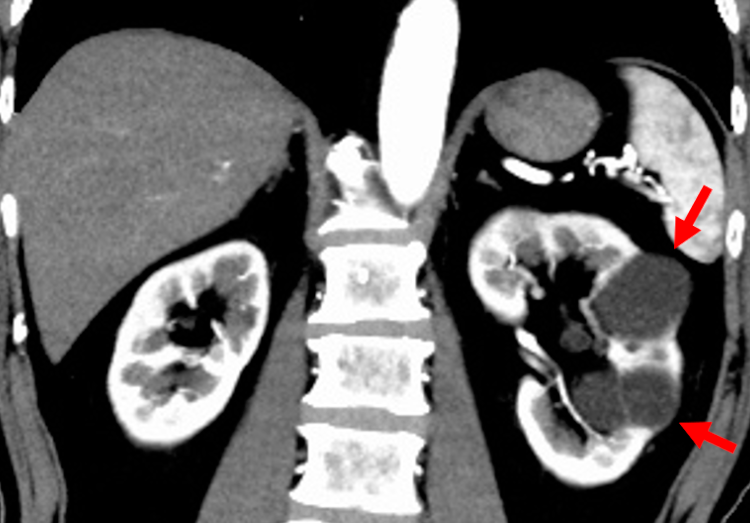

Cisti renali

- Descrizione: Le cisti renali sono sacche ripiene di liquido che si formano nel Parenchima renale. Possono essere semplici (con pareti sottili e contenuto omogeneo) o complesse (con setti, calcificazioni o contenuto denso), distinguendosi dalla malattia policistica ereditaria. Le cisti semplici sono lesioni isolate o multiple, tondeggianti, con pareti regolari e liquido chiaro, comuni negli adulti senza ereditarietà.

Quelle complesse presentano ispessimenti o divisioni interne.